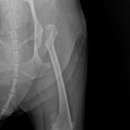

• 24시 에피소드 동물 메디컬 센터 | 만촌동 동물병원 강아지 요골·척골 골절 수술 후기 [24시에피소드동물메디컬센터]

만촌동 동물병원 강아지 요골·척골 골절 수술 후기 [24시에피소드동물메디컬센터] 만촌동 동물병원 ​ 안녕하세요. ​ 풍부한 경험과 따듯한 진료를 바탕으로, 반려동물의 건강하고 행복한 하루하루를 함께 만들어 가는 만촌동 동물병원 24시에피소드동물메디컬센터 입니다. 24시에피소드동물메디컬센터 대구광역시 동구...

에피소드동물메디컬센터(2025-06-26 12:41:00)